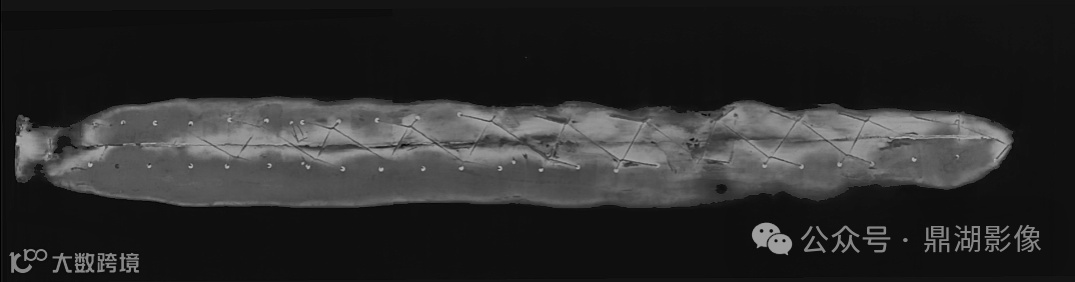

“通过CT扫描,我们第一次清晰地看到棺椁的底面,有一条细小的缝隙和花边。”

原来,Chenet-aa夫人的棺椁并不是紧贴着尸体的!

首先,将木乃伊直立起来,然后用湿气将棺椁软化到足够柔韧的程度,使其能够围绕尸体成型;

接着在棺椁背后切开一个缝隙(从头切到脚),使其展开,将木乃伊置入其中,柔软的棺椁盖在包裹的尸体上,再合上;

最后将棺椁背后的开口 “缝” 起来,在脚部放上一块木板,用钉子固定住,使所有东西都固定在一起。